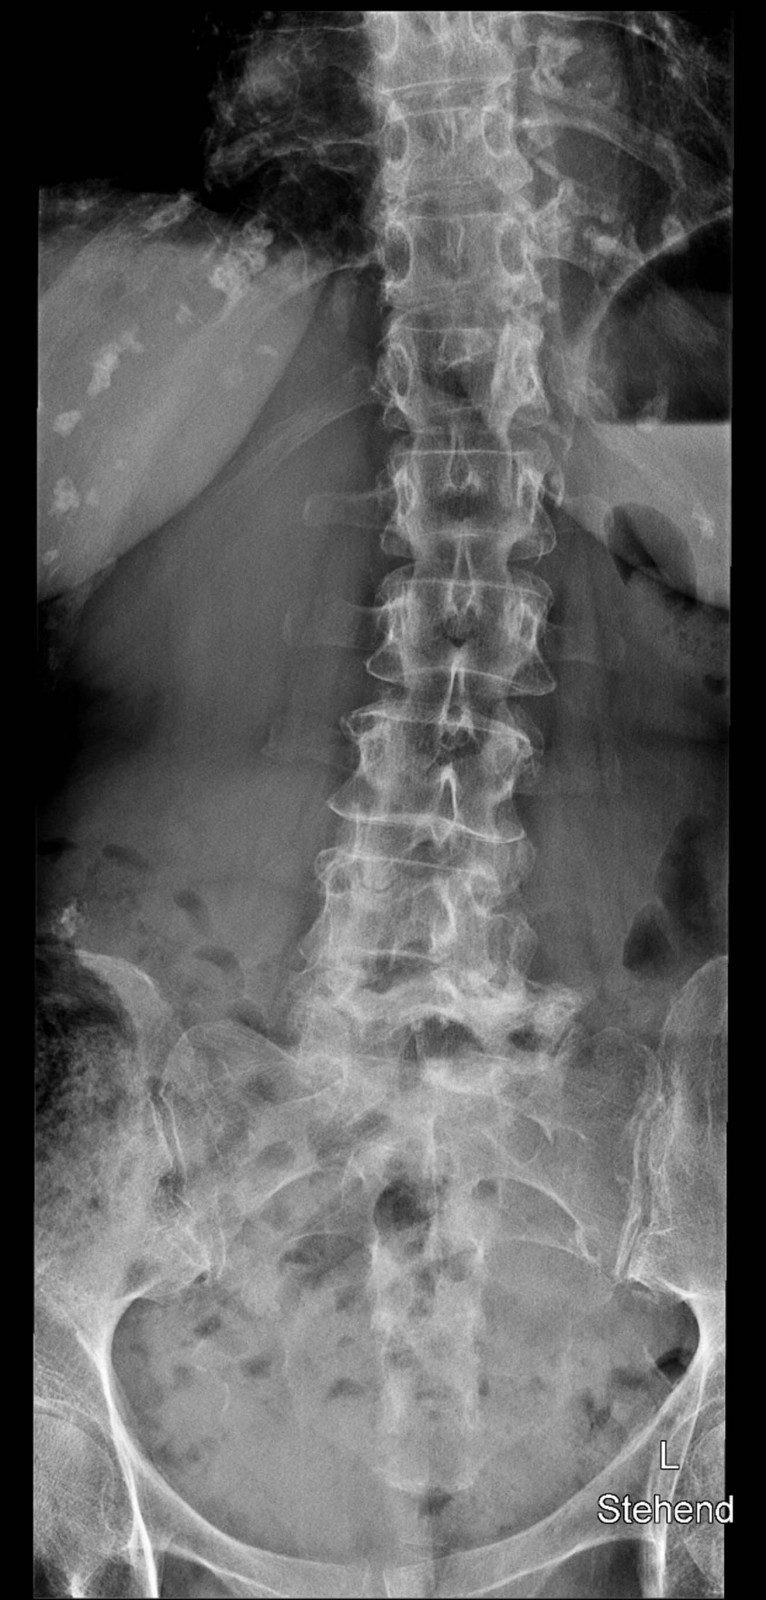

Röntgenfall des Monats März 2017 mit Auflösung

80 jährige Patientin mit chronischen linksbetonten Schmerzen lumbal am Übergang zum Becken